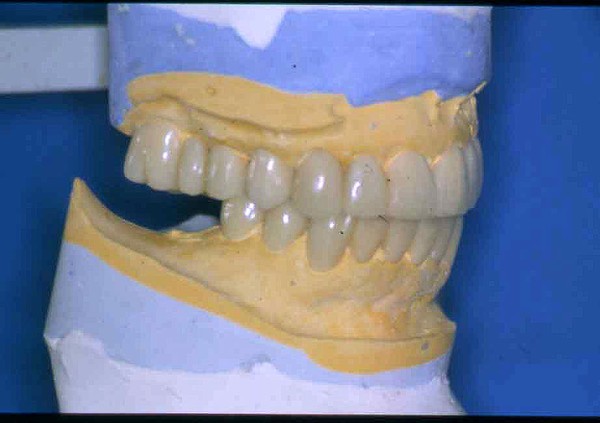

APRECIACIONES DIAGNÓSTICAS EN BASE A LA APERTURA MENTAL DEL CLÍNICO FRENTE A LO QUE EL PACIENTE PROPONE EN MUCHAS OCASIONES , LA DEMANDA DE LOS PACIENTES NOS INCLINAN A FOCALIZAR NUESTRA ATENCIÓN EN LAS PIEZAS DE LAS CUALES EL ENFERMO SE QUEJA. PACIENTE SEXO FEMENINO, 55 AÑOS, SE PRESENTA A LA CONSULTA DERIVADA POR COMPAÑERO GENERALISTA, QUIEN LLEVA MESES PROCEDIENDO A LA «DESINFECCIÓN» DE UN PRIMER PREMOLAR IZQUIERDO, EL QUE SE PRESENTA ABIERTO EN SU CONDUCTO EN EL AFÁN DE PERMITIR EL ESCAPE DE GASES DE UNA GANGRENA PULPAR. A LA INSPECCIÓN CLÍNICA SE OBSERVAN FACETAS PARAFUNCIONALES DE TERCER GRADO , ASINTOMÁTICAS, CON EVIDENTES DIFICULTADES MASTICATORIAS Y ESTÉTICAS , FALTA TOTAL DE SUS MOLARES INFERIORES, Y ADELANTAMIENTO PRONUNCIADO DE SU MANDIBULA, LA QUE CUESTA MANIPULAR DEBIDO A LA SITUACIÓN DE ESPASMO DE CASI TODA SU MUSCULATURA GNATICA. SE ESTUDIA EL CASO RADIOLOGICAMENTE, Y SE RELAJA EL SISTEMA MEDIANTE LAM. DE LONG REALIZANDO UN MONTAJE EN LA ORC OBTENIDA. NO SATISFECHOS CON EL RESULTADO, CONFECCIONAMOS UN JIG DE LUCIA, EL QUE DEJAMOS EN BOCA TODA UNA NOCHE, AL CABO DE LA CUAL REALIZAMOS UN NUEVO REGISTRO REALIZAMOS UN ENCERADO RÁPIDO DEL CASO, Y CONFECCIONAMOS UNA ESTRUCTURA OCLUSAL PLASTICA, QUE ADEMÁS REPONGA EL ASPECTO ESTÉTICO PERDIDO (FÉRULA DE RELAJACIÓN DE COMPONENTE ESTÉTICO), LO QUE PERMITE AL ENFERMO LUEGO DE DOS DÍAS DE USO, NO SOLO CORROBORAR LA COMODIDAD MASTICATORIA Y LA FALTA DE SÍNTOMAS MUSCULARES, SINO TAMBIÉN OBSERVAR APROXIMADAMENTE LA DIFERENCIA ENTRE LA SITUACIÓN INICIAL Y LO QUE PUEDE LOGRARSE MEDIANTE EL TRATAMIENTO. EL PACIENTE ADVIERTE LA MEJORÍA DE LA SITUACIÓN. ACEPTADO POR PARTE DEL MISMO EL TRATAMIENTO SUGERIDO, CREAMOS UN JUEGO COMPLETO DE PROVISORIOS EN BASE AL ENCERADO, Y PROCEDEMOS A TRATAR LA INFRAESTRUCTURA, QUE CONSISTE EN LAS ENDODONCIAS, SUS REFUERZOS A PERNOS DE ORO, LOS ASPECTOS PERIODONTALES DEL CASO, Y DOS IMPLANTES INFERIORES CON TÉCNICA SEMISUMERGIDA ,DE 5 MM DE ANCHO POR 12 DE LONGITUD, CON ANILLO DE ZIRCONIO , A LA ESPERA DE OSTEOINTEGRACIÓN, TRANSCURREN TRES MESES EN EL USO DE UNA NUEVA OCLUSIÓN CONSTITUIDA POR LOS PROVISIONALES, SEGÚN EL ENCERADO, QUE SE REALIZÓ SIGUIENDO LOS CÁNONES DE UNA OCLUSIÓN ORGÁNICA. COMPROBADA LA EFICACIA DE LA NUEVA SITUACIÓN, CON SUS DISCLUSIONES LATERALES Y POSTERO ANTERIORES CORRECTAS, CARECIENDO YA DE SINTOMATOLOGÍA MUSCULAR (SIN MIALGIAS, SIN MIOSITIS, Y CON UN GRADO DE APERTURA DE 4,50 CM), Y SIN SIGNOS EVIDENTES DE DESGASTE SOBRE EL MATERIAL DE LOS PROVISORIOS, ES DECIR: VERIFICANDO QUE EL PACIENTE YA NO BRUXA, VERTICALIZANDO EL CICLO MASTICATORIO /OTORGANDO ORC/ DIMENSIÓN VERTICAL /PROTEGIENDO A LAS PIEZAS `POSTERIORES DE IMPACTOS LATERALES RECIEN ENTONCES , MONTAMOS EN ARTICULADOR SEMI AJUSTABLE LOS MODELOS DE TRABAJO DEFINITIVOS. CONFECCIONAMOS ENTONCES LAS COFIAS INFRA PORCELANA, EN PORCELANA DE ALTA DENSIDAD EN EL SECTOR ANTERIOR Y EN ORO GALVÁNICO PARA EL SECTOR POSTERIOR PARA LUEGO COMPLETAR LA GUIA ANTERIOR , VERIFICANDO LA ALTURA DE LOS INFERIORES RESPECTO DEL LABIO INFERIOR Y CORROBORANDO LOS PUNTOS DE CONTACTOS INTER CANINOS, QUE CENTRALIZAN LA MANDIBULA Y VERTICALIZAN EL CICLO MASTICATORIO Y LAS DISCLUSIONES CANINAS QUE OTORGARÁN PROTECCIÓN A LOS SECTORES POSTERIORES. POSTERIORMENTE CHEQUEAMOS LA DISCLUSIÓN EN PROPULSIVA DE LA GUIA ANTERIOR YA TERMINADA. FIG38 FIG39 UNA VEZ OBTENIDO UN COMANDO ANTERIOR EFECTIVO, COMO LO ES LA GUIA ANTERIOR CON TODOS SUS COMPONENTES, PROCEDEMOS A REALIZAR LAS TABLAS PREMOLAR / MOLAR DE AMBOS LADOS Y OBSERVAMOS QUE LOS PUNTOS INTEROCLUSALES DE CONTACTO SEAN SUFICIENTES Y CUMPLAN SU OBJETIVO DE OTORGAR ESTABILIDAD MESIO DISTAL Y VESTÍBULO LINGUAL. TRANSCURRIDO UN AÑO DE FINALIZADO EL TRATAMIENTO, REALIZAMOS UN CHEQUEO POST OPERATORIO DEL CASO, EN TODOS LOS PARÁMETROS ANTERIORMENTE MENCIONADOS, Y OBSERVAMOS LA ABSOLUTA ESTABILIDAD DEL MISMO EN TODOS SUS NIVELES Y TEJIDOS.